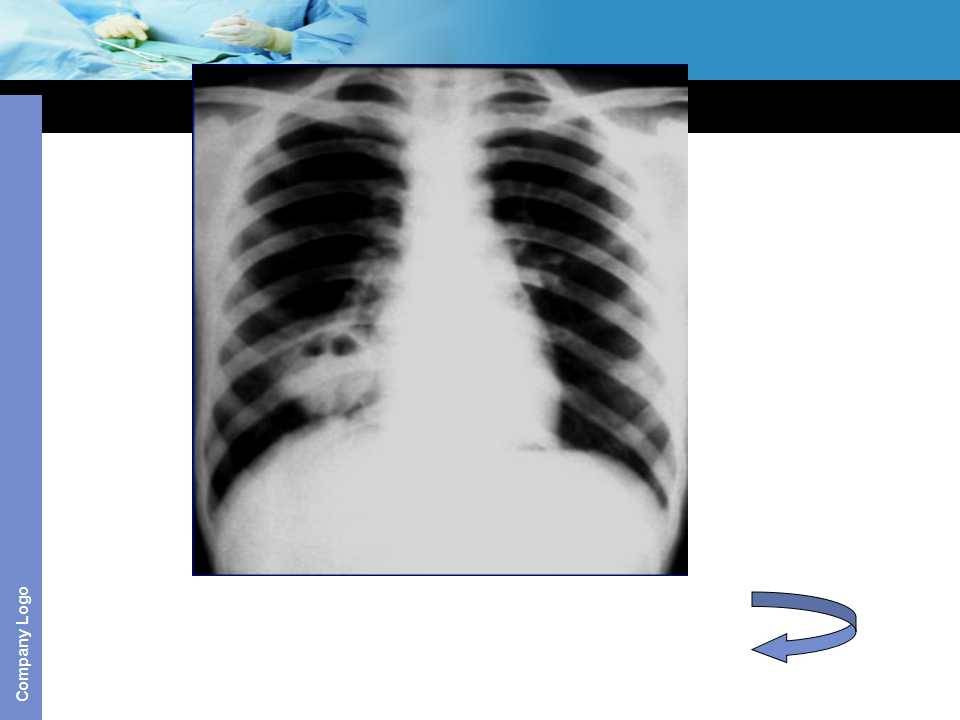

肺癌影像诊断